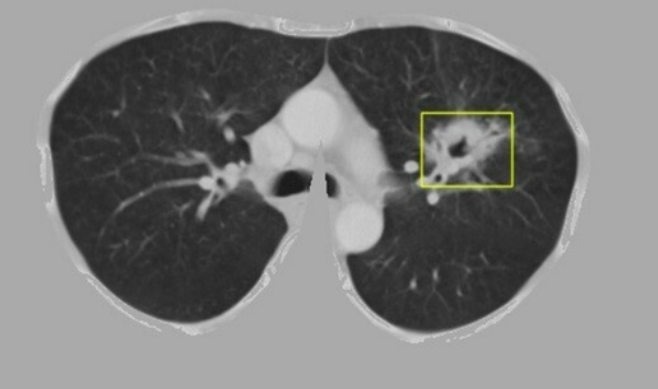

Khối u phổi được hệ thống định vị trong 5-10 giây.

Thông qua thuật toán, hệ thống có khả năng phát hiện vị trí, kích thước khối u phổi trên ảnh chụp cắt lớp, phân loại thành công khối u là lành tính hay ác tính. Hệ thống cũng khoanh vùng sớm điểm tổn thương nghi vấn trên ảnh để các bác sĩ có thể tập trung, nâng cao chất lượng chẩn đoán. Dựa vào tiêu chí đánh giá của ngành y tế, cả độ nhạy và độ đặc hiệu, hệ thống đều đạt trên 96%.